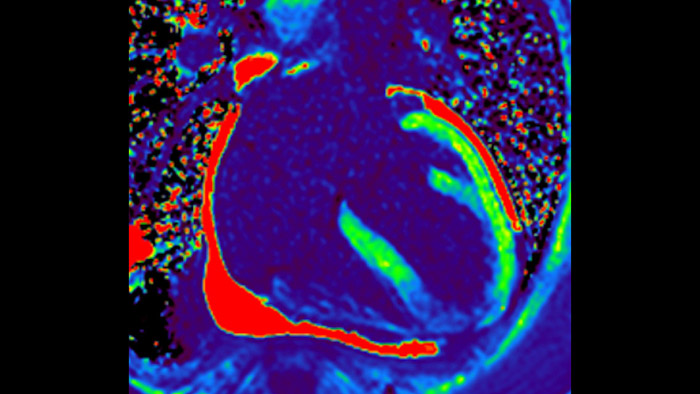

MyoStrain

Today's diagnostics often cannot detect heart dysfunction until symptoms occur. MyoStrain utilises segmental strain to measure 48 segments of the heart and provides physicians with a unique diagnostic tool to help identify regional dysfunction before the heart as a whole is affected.

Quantify Myocardial Strain

IntelliSpace Portal MR Caas5,6 Strain7 assists in patient diagnosis and monitoring by providing global strain parameters such as global longitudinal strain (GLS), global circumferential strain (GCS), and global radial strain (GRS), using short and long axis MR images, as well as describing the myocardium deformation- such as shortening, thickening, and lengthening during the cardiac cycle.